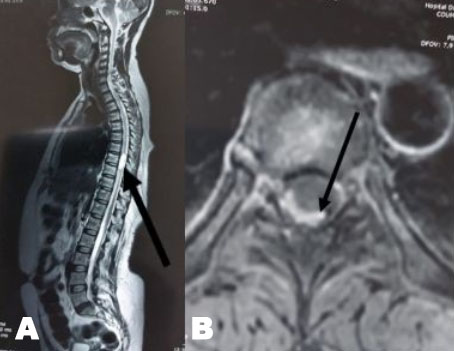

Figure 4: (A) Non-contrast chest CT scan showing diffuse bilateral ground-glass opacities with posterior and peripheral predominance associated to alveolar consolidation with estimated percentage of lesion at 75% consistent with severe COVID-19 pneumonia. (B) Chest CT scan showing bilateral ground-glass opacities and alveolar consolidation along with huge pneumomediastinum (yellow arrow) and subcutaneous emphysema (blue arrows).

A 50-year-old female patient with past history of obesity with BMI at 30 kg/m2 was admitted in our ICU for acute respiratory failure due to COVID-19 pneumonia. There was a history of dyspnea asthenia and cough one week before ICU admission. The patient was initially managed in the pulmonology department with non-rebreather oxygen mask. A non-contrast chest CT scan was performed showing diffuse bilateral ground-glass opacities with posterior and peripheral predominance associated to alveolar consolidation with estimated percentage of lesion at 75% consistent with severe COVID-19 pneumonia (Figure 4A). In front of worsening of his respiratory state, she was transferred to our ICU with moderate acute respiratory failure. Upon admission, her respiratory rate was of 40 breaths/min with struggle signs, SpO2 of 88% under 15 L/min of oxygen with non-rebreather mask, she was conscious with stable hemodynamic state. Blood test results showed a CRP of 81 mg/L, leukocytes of 18.400/mm3, D-dimer of 290 µg/L and the ABG showed respiratory alkalosis with pH: 7.47, PaO2: 51 mmHg, PaCO2: 32 mmHg, HCO3−: 23 mmol/L, and SaO2: 88%. The patient was put initially under NIV (PS of 20 cmH2O, PEEP of 6 cmH2O, and FiO2 100%); antibiotics, dexamethasone 6 mg/12 h, anticoagulation and prone positioning. At day 6 of ICU stay she was intubated in front of NIV failure using direct laryngoscopy with no difficult airway management, no bougie or stylet were used and 7.5 cm tracheal tube was inserted at level 23 of dental arch. The patient was ventilated with protective ventilation with VAC mode (Vt: 6 mL/kg of PBW, PEEP: 10 cmH2O, RR: 26 breaths/min, and FiO2 100%). Under protective ventilation, peak airway pressure (PIC) was of 28 cmH2O, plateau pressure (P.Plat) of 24 cmH2O, and driving pressure (DP) of 14 cmH2O. She was immediately put under continuous infusion of sedation and neuromuscular blockers. Four hours after intubation a subcutaneous emphysema appeared in the neck, chest wall, and in the abdomen. On examination there was a symmetric crackle on thoracic auscultation without silence, respiratory mechanics showed increasing in PIC of 35 cmH2O and P.Plat of 30 cmH2O without worsening of hemodynamic state. A non-contrast chest CT scan was performed showing: huge PM reaching the right peritoneal space associated with an important subcutaneous emphysema in the neck and thoraco-abdominal region with suspected tracheal perforation with worsening of the ground-glass opacities and inferior alveolar consolidation, no pneumothorax was associated (Figure 4B). In front of the deep hypoxemia (PaO2/FiO2 of 80 and SpO2 at 86% with deep decrease of SpO2 till 50% while ventilator disconnection attempts), a flexible bronchoscopy to identify the tracheal breach wasn't possible. The attitude was to introduce the tracheal tube till 27 level of dental arch to plug the tracheal breach with the balloon (according to the CT thoracic scan data we recommend us to introduce the tracheal tube by 4 cm approximately), decreasing the PEEP to 6 cmH2O with close monitoring of the hemodynamic and respiratory state. The evolution was marked by the regression of the subcutaneous emphysema five days later and the improving of the respiratory state (PaO2/FiO2 of 200, SpO2 at 95% and peak pressure of 28 cmH2O). A non-contrast chest CT control scan was performed showing a significant regression of the PM and the subcutaneous emphysema with persistent severe lung lesion with ground-glass opacities and consolidation images (Figure 5). The patient was maintained under protective ventilation with difficult weaning. The evolution was marked by a septic shock due to ventilator acquired pneumonia, and she passed away at day 18 of ICU stay in a refractory shock.